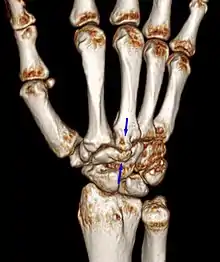

Carpal boss VR-3D-Reconstruction

Carpometacarpal bossing (or metacarpal/carpal bossing) is a small, immovable mass of bone on the back of the wrist. The mass occurs in one of the joints between the carpus and metacarpus of the hand, called the carpometacarpal joints, where a small immovable protuberance[1] occurs when this joint becomes swollen or bossed.

The joint between the index metacarpal and the capitate is a fibrous non-mobile joint. Some people have a gene that leads to this growth. It looks like arthritis (bone spurs on each side of the joint) on X-ray. It looks like a ganglion on the hand, but more towards the fingertips.

The carpometacarpal joint is usually found at the base of the second and third metacarpal bones at the point where they meet the small bones of the wrist.[2]

Carpometacarpal boss is uncommon and there is not much scientific data. Its etiology has yet to be fully defined, but can be congenital in the form of an accessory ossicle (os styloideum) or may be acquired from trauma, repetitive use, or degenerative osteophytosis.[3] The condition usually begins to show in the 3rd or 4th decade.